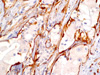

CASO N° 1 (Dr. Jair e Dr. Delgado)

Paciente do gênero masculino, 44 anos de idade, apresenta uma lesão no palato duro e palato mole.